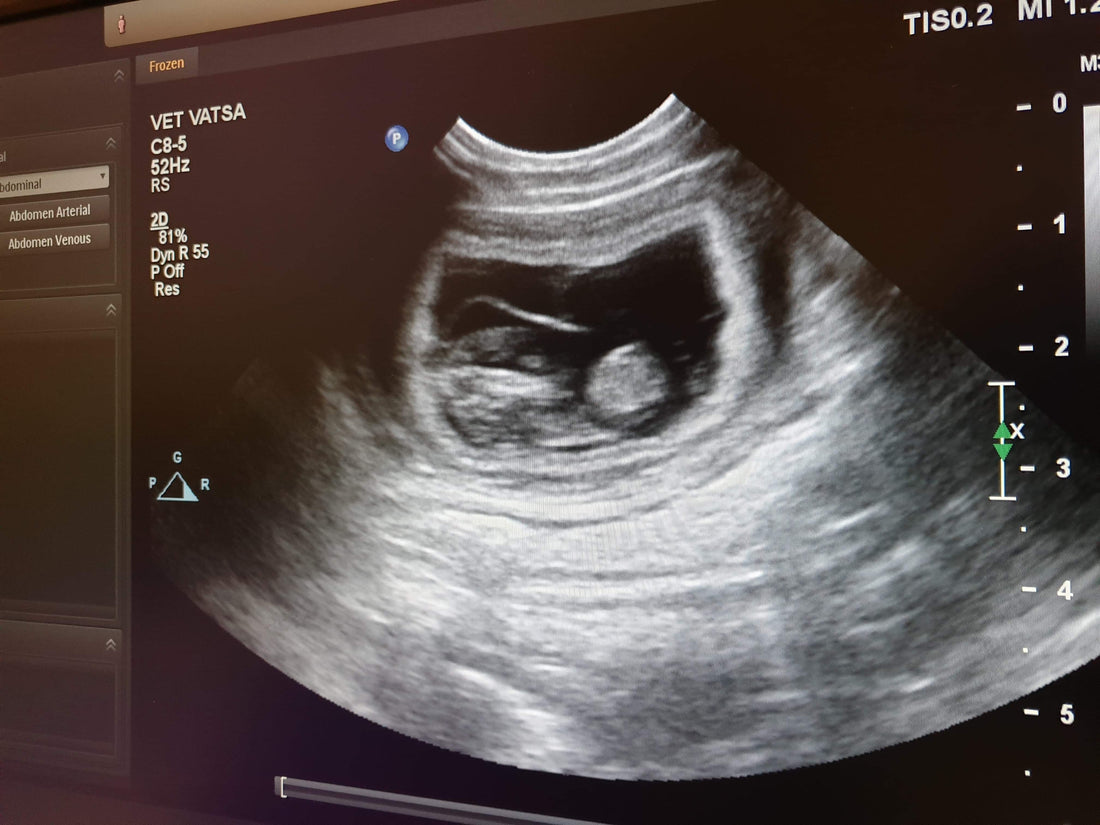

Redigera: 3-4 valpar sågs i ultraljudet!